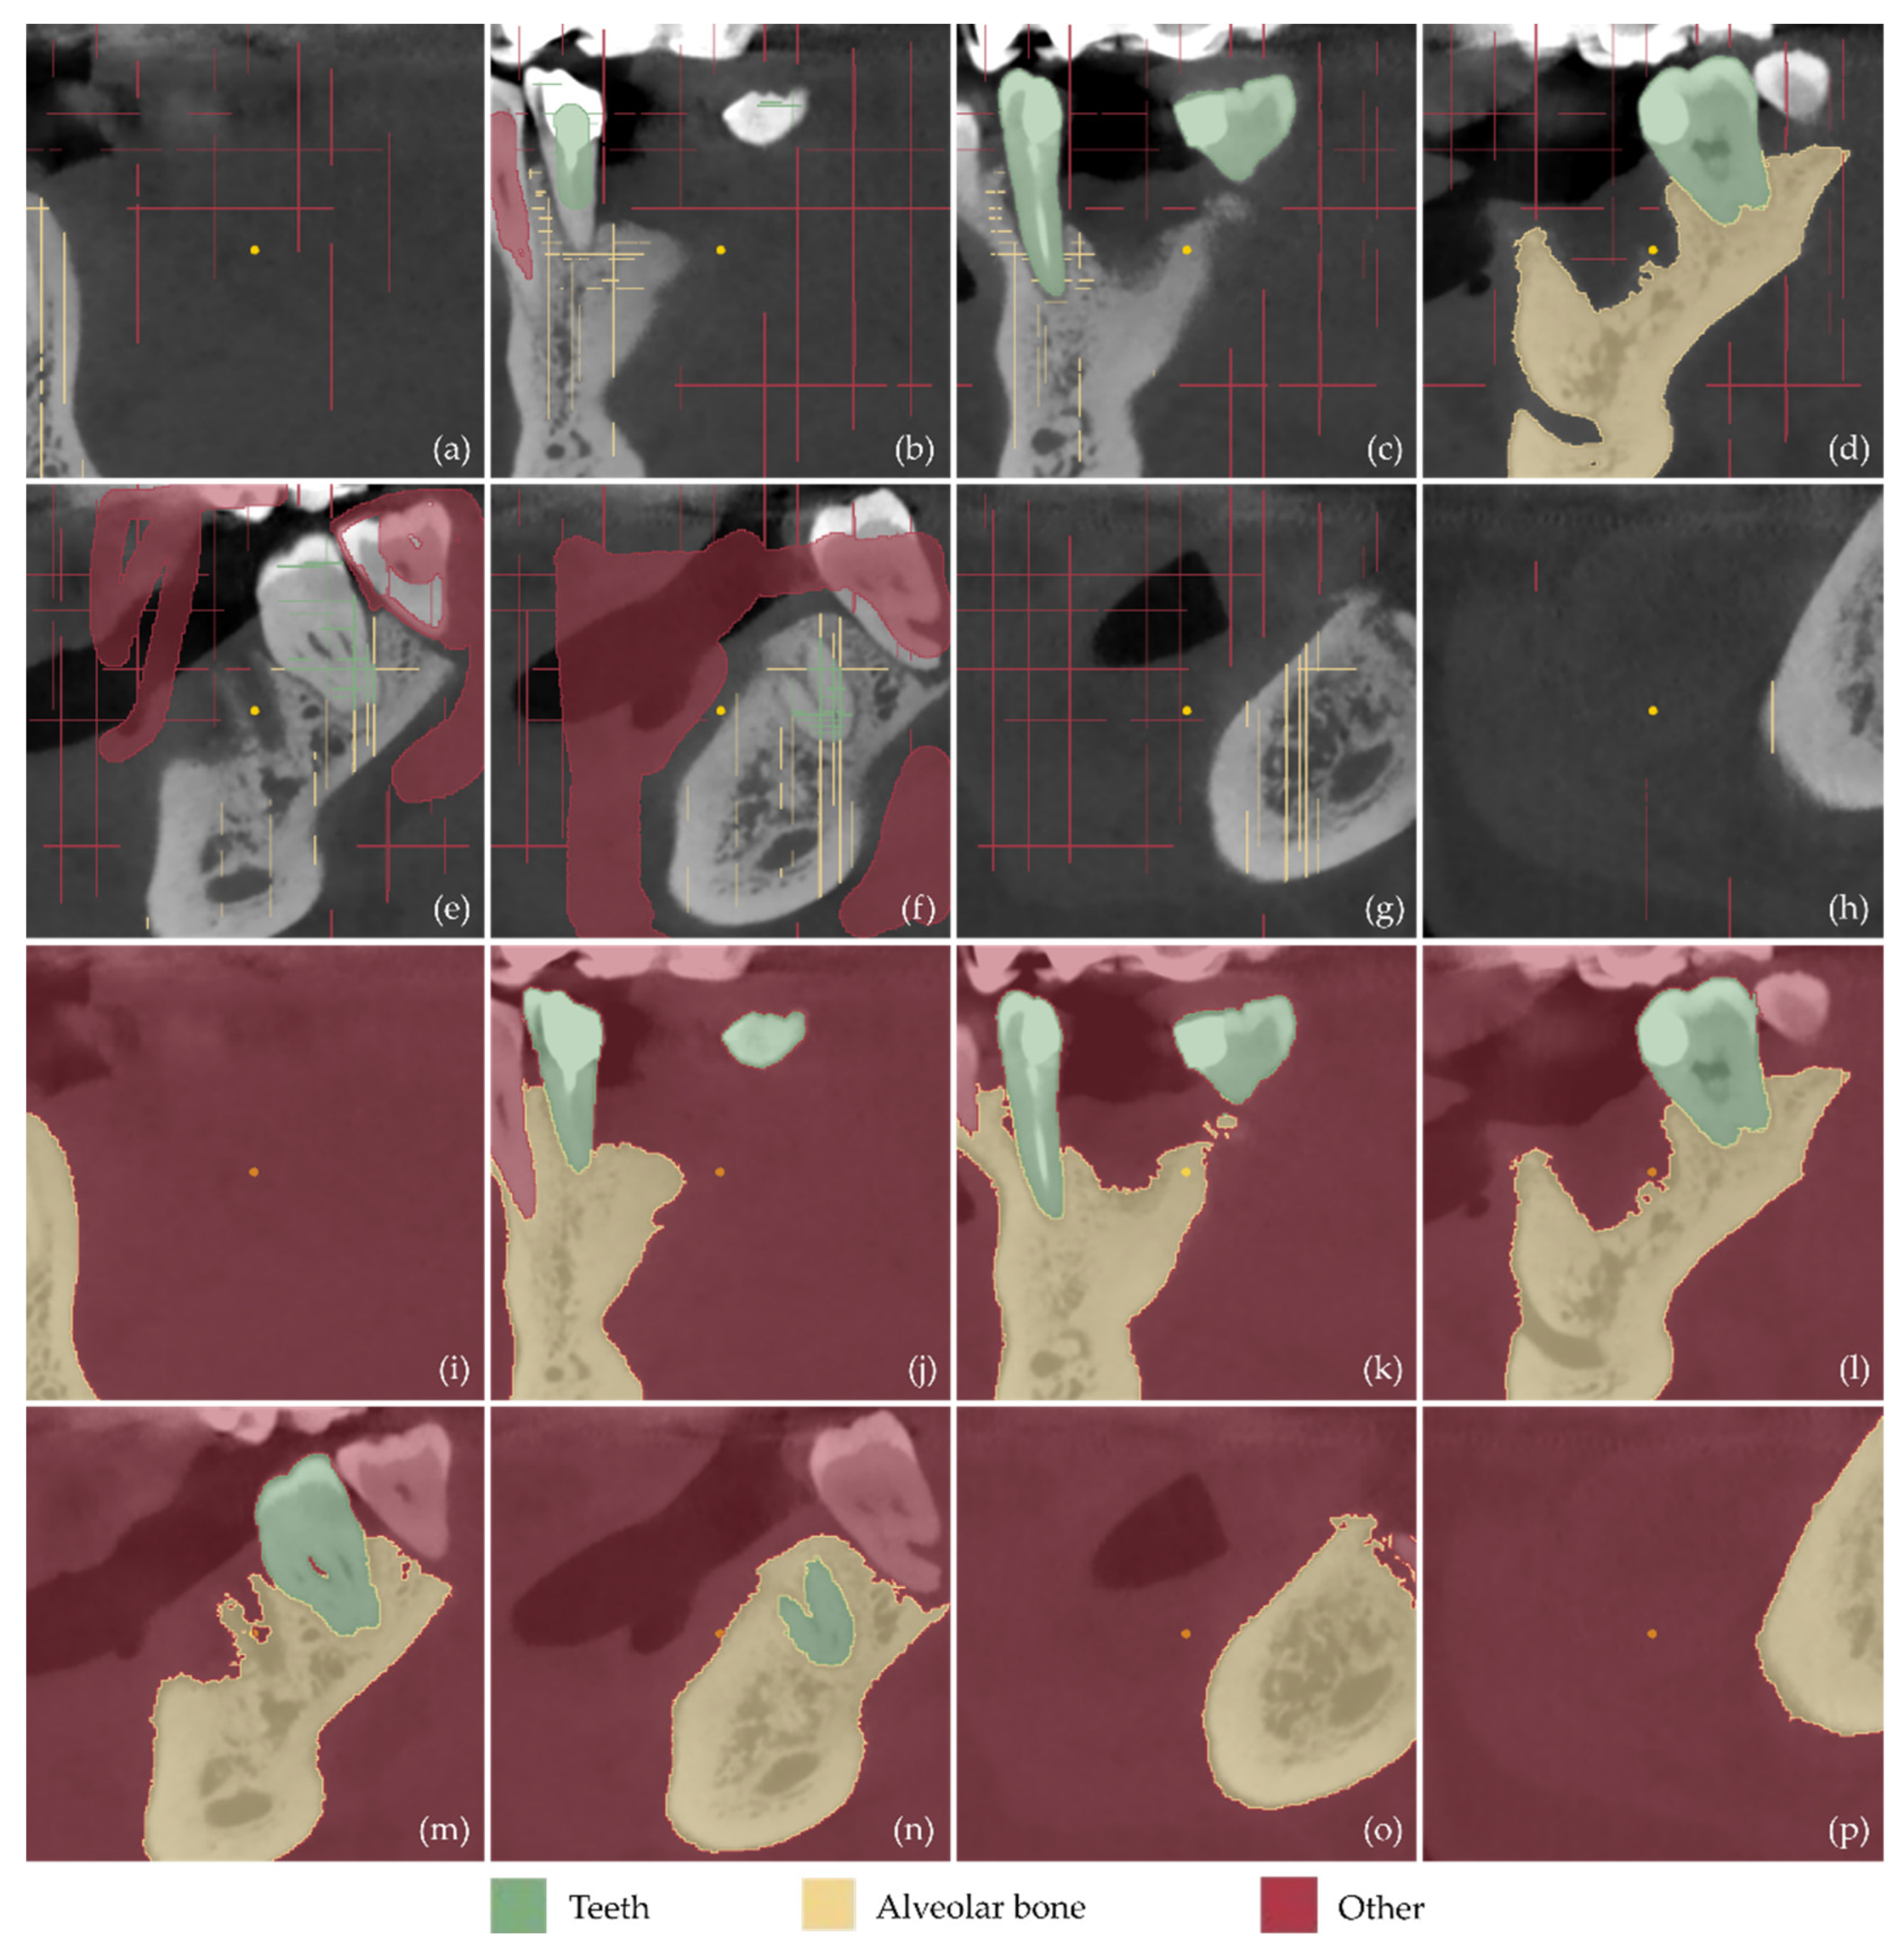

2.1. 3D Modeling of Periodontal Defects

- Definition of the region of interest by cropping the corresponding volume defined in the CBCT dataset.

- Definition of three segments: Teeth, alveolar bone, and “other”, including all the other areas of the oral system, depicted in the CBCT cropped images.

- Definition of samples for the aforementioned segments for a small subset of CBCT images (e.g., 30 images: 10 per reference plane), through a combination of automatic (thresholding) and manual procedures.

- Initialization of the “Grow from seeds” method [52].

- Iterative correction and update of the result of the “Grow from seeds” method until the visual inspection of the result satisfies the user.

- Conversion of the segmentation results for the teeth and alveolar bone segments into 3D models (meshes) in STL format.

3.1. 3D Model of Hard Tissues in the Area of the Periodontal Defects